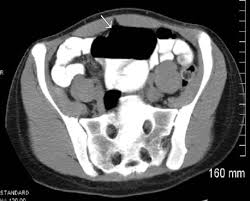

The patients symptoms resolved quickly after colonoscopic reduction and elective laparoscopic surgery was performed 18 days after admission. A planned surgery is not fun but an emergency surgery for a twisted colon would be even worse. Based on these findings we diagnosed cecal volvulus caused by mobile cecum syndrome. On the other hand a chronic form of mobile cecum syndrome which is the most common form reported a history of intermittent crampy abdominal pain distension and constipation. However it may be present as a precursor of frank cecal volvulus in approximately 50 per cent of the cases. 102 patients were followed up to 15 years after the operation. Abstract Five cases of mobile cecum syndrome are presented. Ehlers-Danlos syndrome hypermobility type EDS-HT mobile cecum ptosis laparoscopic. The following symptoms may be experienced with cecal volvulus.

On the other hand a chronic form of mobile cecum syndrome which is the most common form reported a history of intermittent crampy abdominal pain distension and constipation. It lies at the junction of the small and the large intestines and is the origin of the appendix. Ballooning abdomen abdominal distension. Thats about as mobile as you can get. The following symptoms may be experienced with cecal volvulus. A mobile caecum and ascending colon is a rare congenital abnormality. The cecal volvulus represents the acute form with typical feature of a bowel obstruction that needs immediate operative treatment.